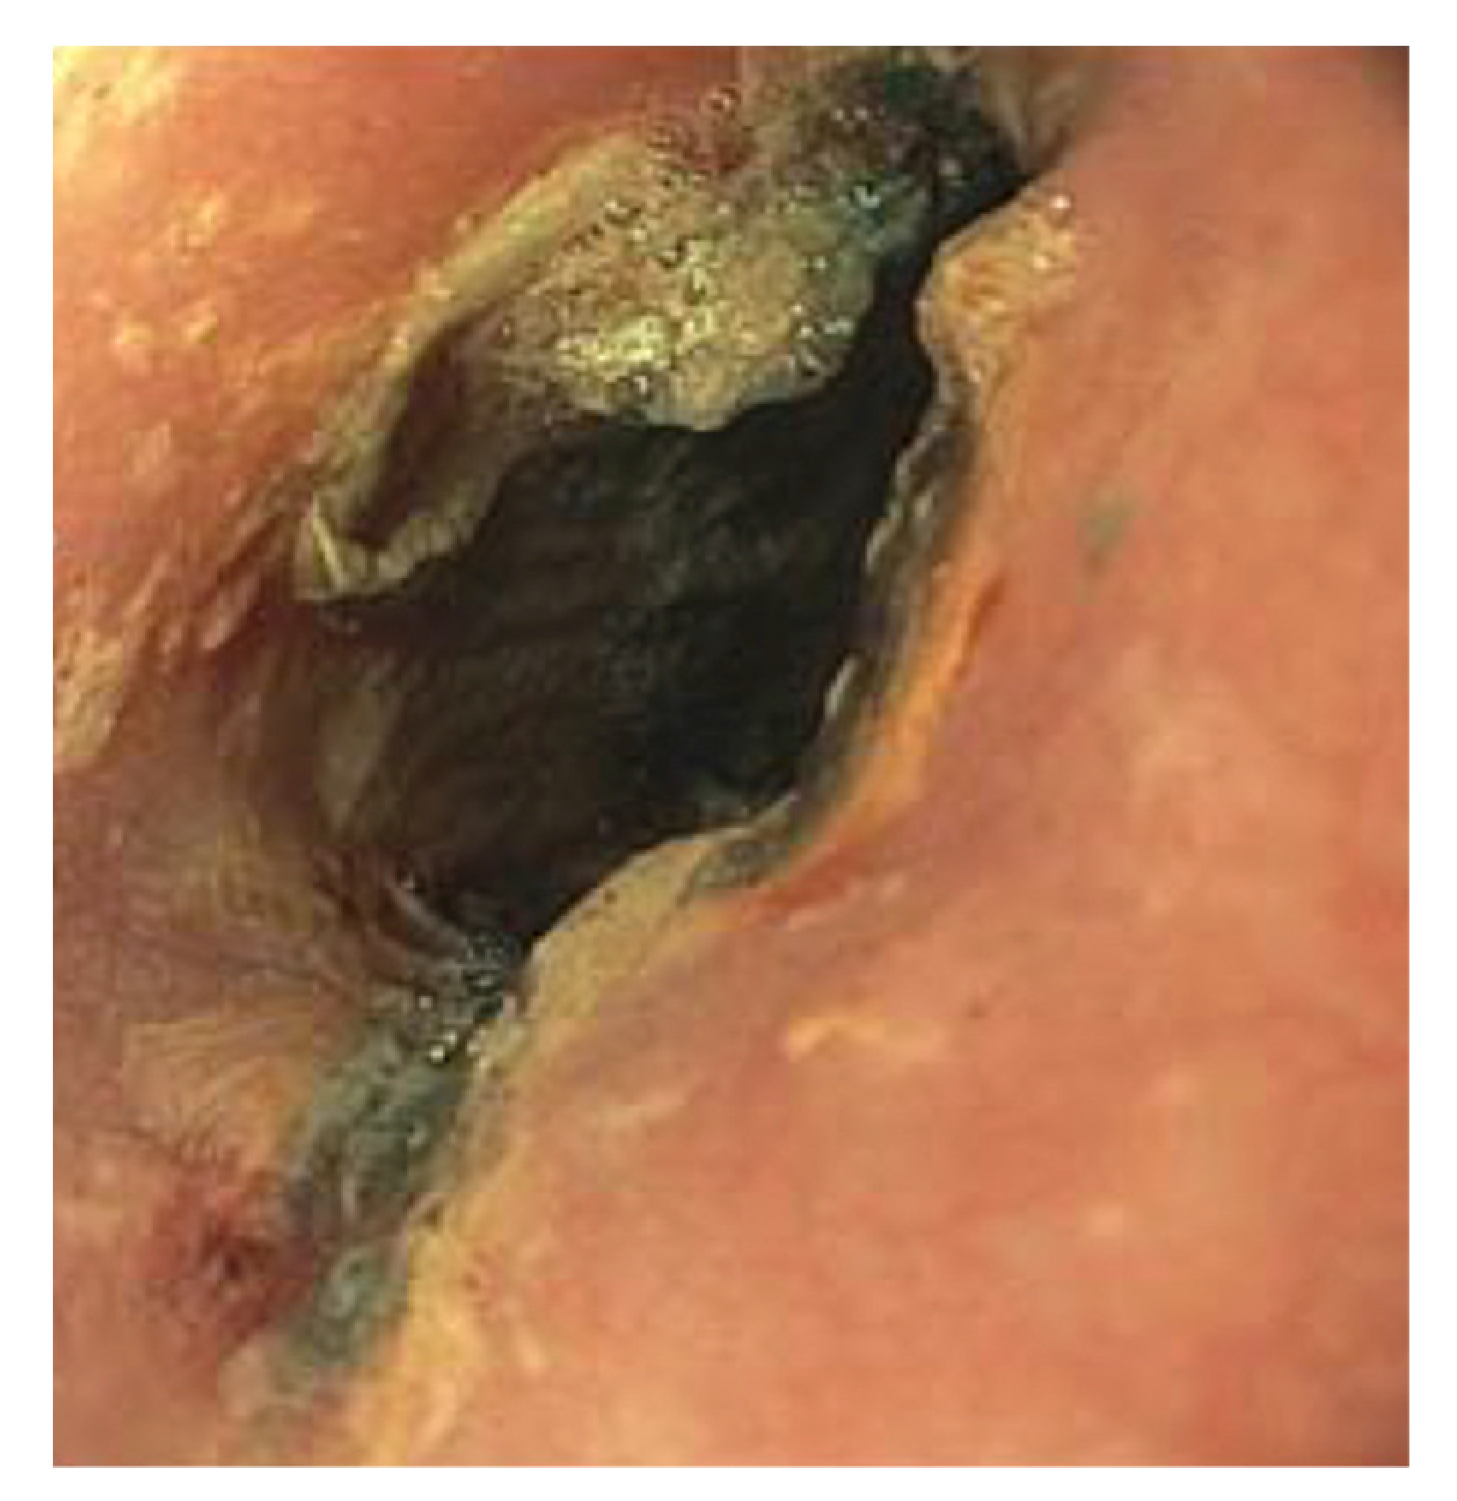

2. Case Presentation